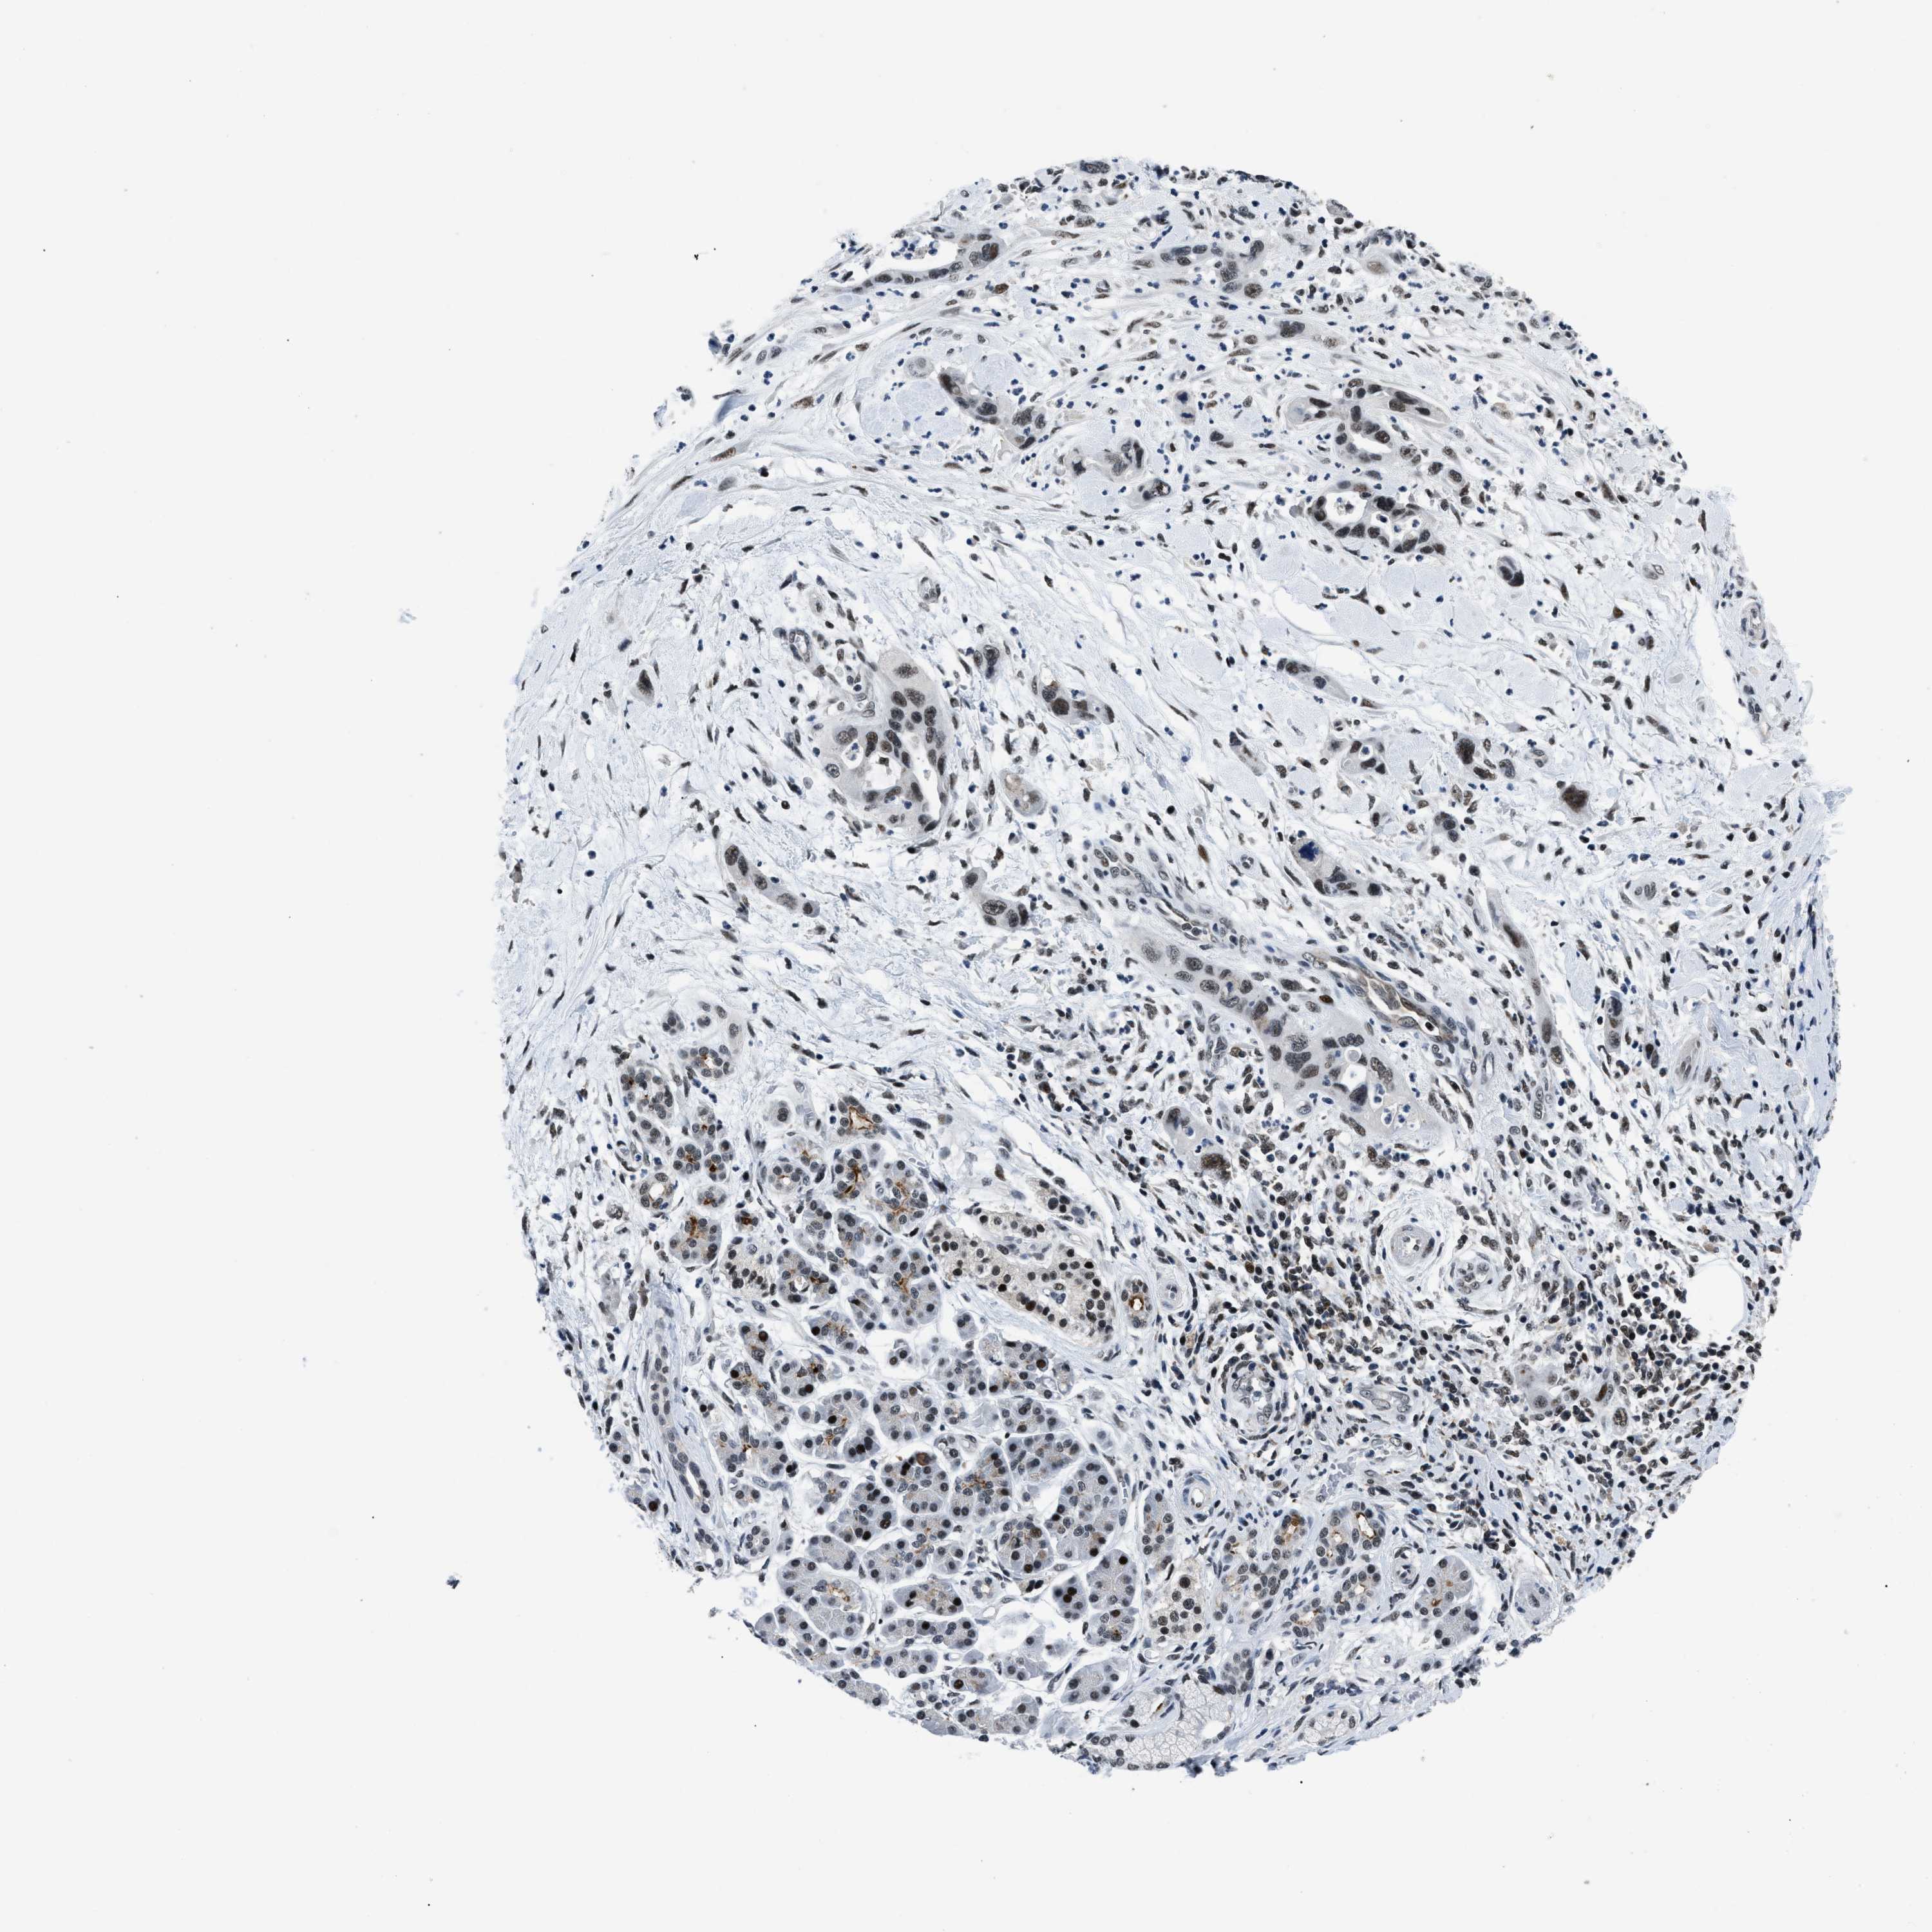

PANCREATIC CANCER - Protein expressioni

A mouse-over function shows sample information and annotation data. Click on an image to view it in a full screen mode. Samples can be filtered based on level of antibody staining by selecting one or several of the following categories: high, medium, low and not detected. The assay and annotation is described here.

Note that samples used for immunohistochemistry by the Human Protein Atlas do not correspond to samples in the TCGA dataset.

Antibody stainingi

Antibody staining in the annotated cell types in the current human tissue is reported as not detected, low, medium, or high, based on conventional immunohistochemistry profiling in selected tissues. This score is based on the combination of the staining intensity and fraction of stained cells.

Each image is clickable and will lead to virtual microscopy that enables deeper exploration of all samples and also displays staining intensity scores, fraction scores and subcellular localization as well as patient and tissue information for each sample.

Antibody HPA018248

Antibody HPA019127

Antibody CAB009196

Staining

High

Medium

Low

Not detected

Intensity

Strong

Moderate

Weak

Negative

Quantity

>75%

75%-25%

<25%

None

Location

Nuclear

Cytoplasmic/membranous

Cytoplasmic/membranous,nuclear

Adenocarcinoma, NOS

Adenocarcinoma, metastatic, NOS